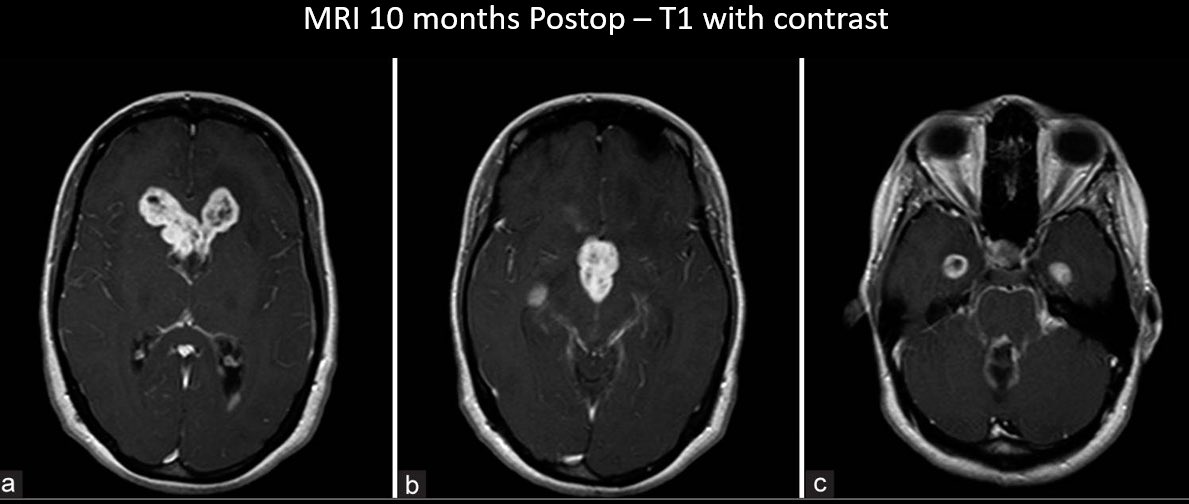

How would you manage this 42F w/ intracranial recurrence of optic nerve sheath meningioma initially biopsied at OSH 5 yrs ago. R eye blind, L 20/20, EOMI. Observation? Radiation? If surgery, approach/extent of resection? #Neurosurgery #MedEd #MedTwitter @EvaWuMD @TheJNS @WFNSHQ